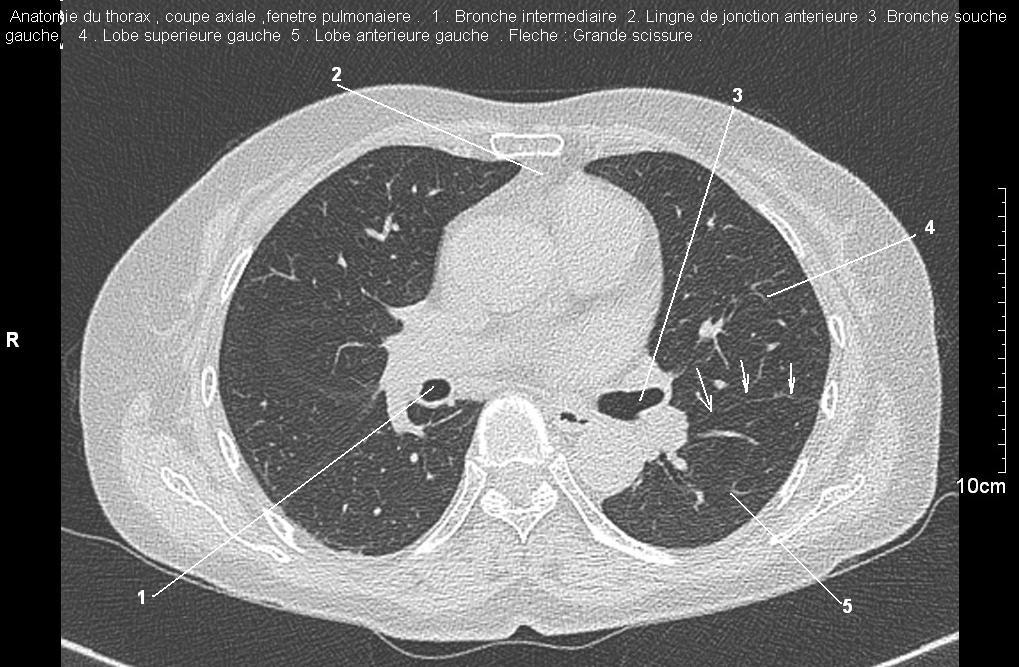

Radioanatomie pulmonaire ( image radiologie thoracique normale )- La Tomodensitometrie du  thorax ( coupes axiales fenetre pulmonaire )

Les fenetres parenchymateuses permettre d'etudier anatomie du poumon et juger sur les lesions du parenchyme pulmonaire en coupes axiales de 0,5-1cm sur le thorax .